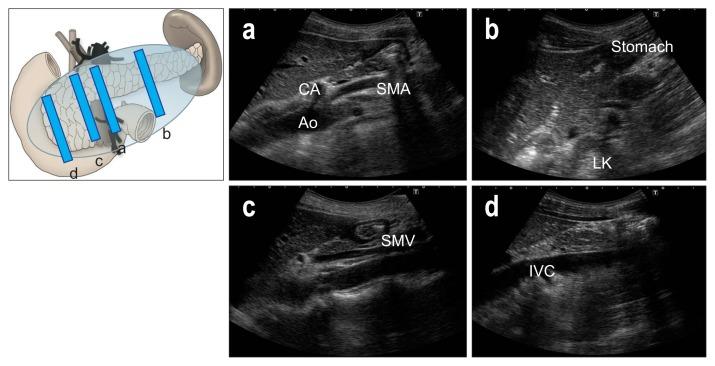

As ultrasound (US) is simple and less invasive than other imaging modalities, this technique is widely used for mass screening. However, visualizing the entire pancreas due to complicated anatomy, obesity and overlying gas can be difficult. US plays a key role in the diagnosis of pancreatic carcinoma (PC), of which tumors smaller than 10 mm (TS1a) and pancreatic carcinoma are expected to have good prognosis. To detect these forms of PC, main pancreatic duct (MPD) dilatation (3 mm or more) and pancreatic cysts (5 mm or larger) are US findings of high-risk individuals (HRIs), and these subjects should be observed periodically. Scanning maneuvers are also important for both screening for PC and follow-up of HRIs. As lesions in the groove area and ventral pancreas do not affect the MPD or extrahepatic bile duct, we should pay attention to these areas. Visualization of the tail is also challenging due to gas and stool in the alimentary tract. As the position of the pancreas changes depending on the body posture, and several different body positions should be employed, such as the right lateral decubitus, sitting, and upright positions, rather than only applying strong compression with the transducer. In cases with poor visualization, the liquid-filled stomach method is highly recommended.

由于超声(US)比其他成像方式简单且侵入性更小,因此该技术被广泛用于大规模筛查。然而,由于胰腺的复杂解剖结构、肥胖和上方气体的影响,很难对整个胰腺进行可视化。US 在胰腺癌(PC)的诊断中起着关键作用,其中直径小于 10mm(TS1a)和胰腺神经内分泌肿瘤的肿瘤预计具有良好的预后。为了检测这些形式的 PC,主胰管(MPD)扩张(3mm 或更大)和胰腺囊肿(5mm 或更大)是高危人群(HRIs)的 US 发现,这些患者应定期观察。扫描手法对于 PC 的筛查和 HRIs 的随访也很重要。由于沟区和胰头区域的病变不会影响胰管或肝外胆管,因此我们应该注意这些区域。由于消化道中的气体和粪便,尾部的可视化也具有挑战性。由于胰腺的位置随体位变化而变化,因此应采用几种不同的体位,如右侧卧位、坐位和立位,而不是仅用探头进行强力压迫。在可视化效果不佳的情况下,强烈推荐使用充满液体的胃法。